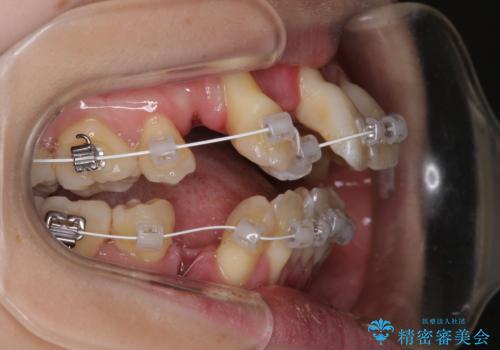

- 審美装置

歯根露出が顕著であったため、歯の移動は早く、スムーズに治療を終えられるかと思いましたが、歯槽骨が硬く、治療は長期間に及びました。

過剰に力をかけ続ける事態となり、一部の歯では変色したり、神経が失活したりとトラブルが続きました。

それでも当初とは比べものにならないほど、綺麗な歯列に仕上げることができました。